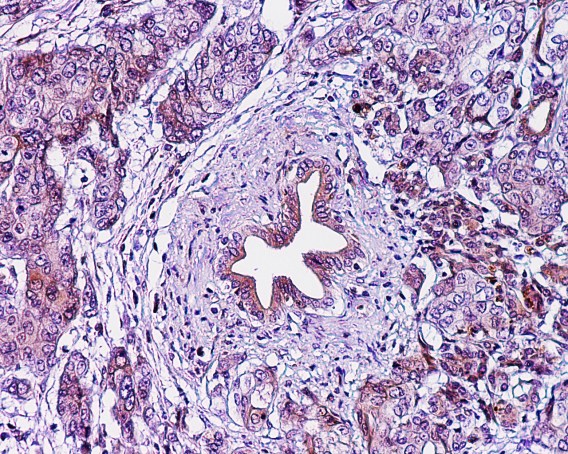

A pancreatic ductal adenocarcinoma

Credit: The lab of Ken Zaret, Perelman School of Medicine, University of Pennsylvania

But the current study by researchers at the University of Pennsylvania used late stage pancreatic cancer cells as their iPSC cell source. One of the reasons pancreatic cancer is thought to be so deadly is because it’s usually diagnosed very late when standard treatments are less effective. So, this team aimed to reprogram the cancer cells back into an earlier stage of the cancer to hopefully find proteins or molecules that could act as early warning signals, or biomarkers, of pancreatic cancer.